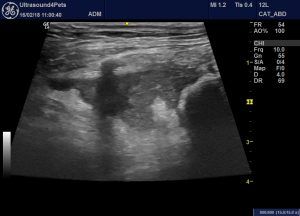

This should give a view something like:

Oblique/transverse view of the body of pancreas and cranial duodenal flexure through an intercostal space on the right.